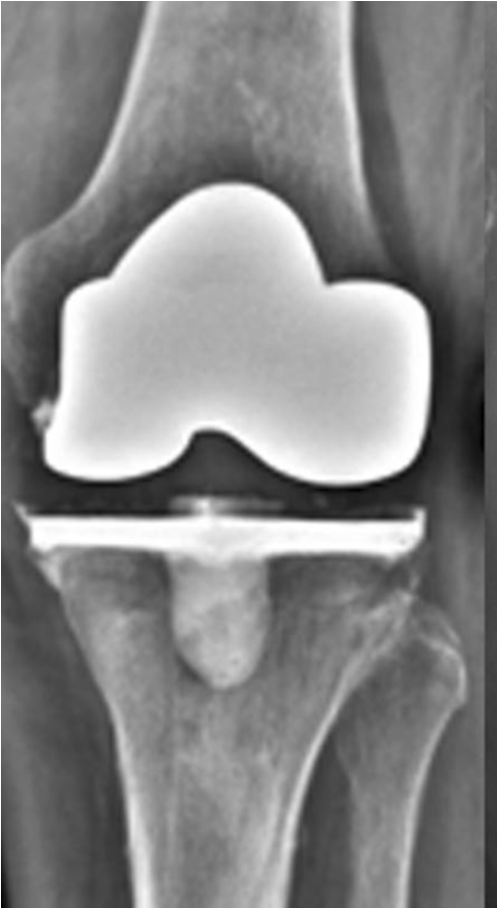

The knee is closed in a standard fashion with one deep drain, which is closed for the first 6 hours. Systemic AB therapy is started in the OR. A long brace which allows flexion is added only if the knee would not be stable enough. X-rays in two layers are performed either intra OR ore before mobilization to confirm proper positioning of the implant (Fig 14)

Final Implantation

After planning and preparing the revision implant with stems, metal blocks, and metaphyseal fixation options the final implantation is done in a standard way as described in a previous study [12]. Although depending on bony defects and ligament situation a primary implant might be possible, we routinely use a revision implant which allows additional stem fixation and higher constraint when needed. “Less constrained possible” is used for the final implantation therefore, our favorite implant is a varus/valgus constrained design which allows the use of a PS insert in balanced knees (Fig 16).

RHK would be used only in knees with insufficient extensor mechanism, global instability, severe bone defects AORI type 3, recurvatum or joint line changes > 8 mm. This is very rare in this scenario with SA knees. Removal of the AB prosthesis should be possible very easy, otherwise the implantation was not done “press fit” (Fig 17).

Own Results

16 consecutive patients with active SA had been treated with a two stage TKA procedure between 2006 and 2016. Mean FU was 6.1 years (range 2.0 to 9.9 years) and no patient was lost for FU. The median number of prior open or arthroscopic debridement before the two-stage procedure was 2 (range 1 to 6). All patients showed clinical and laboratory sign of a septic arthritis with severe chondrolysis or OA. The infection was cured after 6 weeks for all knees. Final implantation was performed between 6 to 12 weeks in all patients with a varus/valgus constraint implant (NexGen LCCK, Zimmer, Warsaw). Only three knees needed a CCK insert, whereas 13 knees were stable enough for using a PS insert only. For the AB spacer and final implantation no intra- or postoperative complications occurred.

No patient needed a brace for mobilization and all patients where highly satisfied with their pain and function in the interval. They reported residual pain only, were able to walk without crutches with good ROM and many of them even ask if the final implantation will be necessary. After final implantation the patients showed comparable outcome to normal primary knees. The mean KSS objective and function score increased significantly from preop situation (58/17) to after spacer implantation (75/46) and further improved after TKA implantation at the final FU (96/86). The mean VAS score was 6.5 preop, decreased to 2.1 after the spacer and 1.2 after TKA at final FU. At final FU no clinical or radiographic signs of infection, loosening or osteolysis could be identified in all patients.